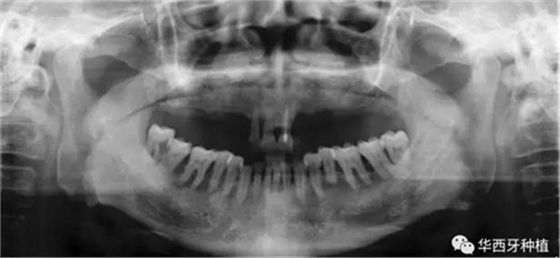

吳教授首先就全口牙缺失病種自身具有的特點,進行了總結(jié)。特別強調(diào)了嚴重的牙槽骨骨質(zhì)萎縮,其結(jié)合上下頜骨的解剖結(jié)構(gòu)(上頜竇,下齒槽神經(jīng)管)后導致的種植區(qū)骨量不足。

接下來吳教授分別針對幾種具有不同特征的病例,進行分析、設(shè)計與病例回顧。對于不同骨量缺失的全口牙缺失患者,可選的種植修復(fù)方式有較為傳統(tǒng)的組牙種植修復(fù)、種植覆蓋義齒修復(fù)、all-on-four或all-on-six的修復(fù)方式。拓寬了我們在全口牙缺失病例種植與修復(fù)治療中的視野與選擇。

對于骨量較好的患者,選擇設(shè)計與手術(shù)方法較為簡單的傳統(tǒng)的組牙種植修復(fù),過程較為便捷,遠期效果穩(wěn)定。但是時間與經(jīng)濟成本高,并且在全口牙缺失患者口內(nèi),由于參照物較少,種植體的位置,共同就位與平行度的選擇與構(gòu)建均存在一定難度。